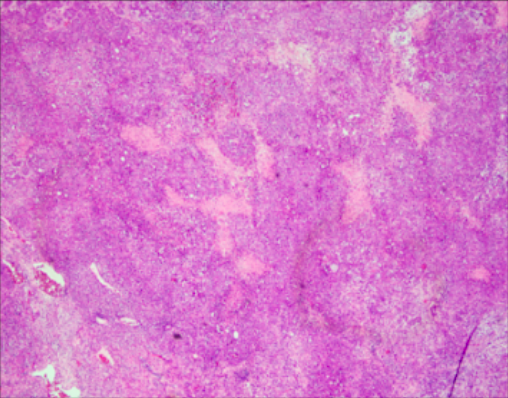

This tumor is rare, occurs almost exclusively in women of reproductive age and children (median: 25 years). Tumors are usually large, solid, fleshy and tan to white to grey, often with hemorrhage, necrosis and cystic degeneration.

Tumor cells grow in sheets, nests, cords, and trabeculae. Scattered follicle like spaces with eosinophilic or basophilic secretions are often seen. Cells have monomorphic round, ovoid or occasionally spindles nuclei with vesicular chromatin, small nucleoli, scant cytoplasm, and brisk mitotic activity. Large cells are present in half of these tumors, which are designated “small cell carcinoma, large cell variant” if the large cells are predominant. Immunohistochemistry reveals absence of SMARCA4 (and SMARCA2) in almost all tumors, along with diffuse expression of WT1, p53, and p16 and variable expression of claudin-4, SALL4, keratins, EMA (especially in the large cell component), CD10, calretinin, and all neuroendocrine markers. Inhibin and TTF1 are negative. Prognosis is poor.